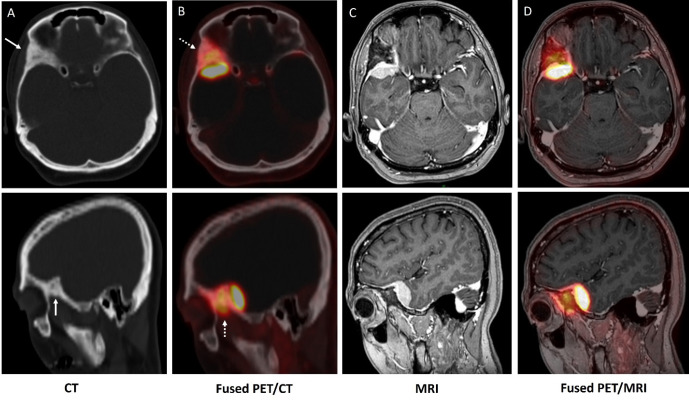

Meningiomas express the somatostatin receptor (SSTR). The utilization of SSTR ligands, specifically Gallium-68 (68Ga) isotope, a radioactive isotope (68Ga)-DOTA-labeled peptides, has demonstrated exceptional diagnostic precision for the detection of meningiomas, primarily due to the absence of normal brain and bone activity. We report a case of a 48-year-old woman with sphenoid wing meningioma who underwent 68Ga-DOTA TOC positron emission tomography (PET) for tumor delineation. 68Ga-DOTA TOC PET shows SSTR-avid meningioma in the right sphenoid/anterior temporal region with significant hyperostosis with high expression of SSTR in the bone. 68Ga-DOTA TOC uptake in the hyperostosis signifies bone infiltration rather than reactive changes. 68Ga-DOTA PET provides a better assessment of osseous involvement and provides additional information in terms of meningioma extent and planning for further management.